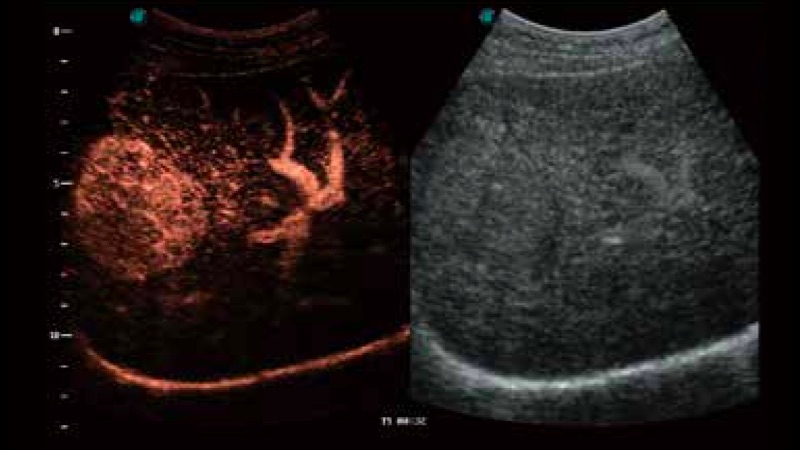

開立醫(yī)療通過不斷的技術(shù)創(chuàng)新,為大眾的生命健康提供持續(xù)關(guān)愛。P12 Plus采用全新一代超聲成像平臺,新平臺旨在將真實(shí)還原組織解剖結(jié)構(gòu)作為首要目標(biāo)。平臺采用全新集成化硬件模塊,搭載新一代芯片,系統(tǒng)性能得到大幅提升,為您的診斷提供了豐富的臨床信息。優(yōu)異的圖像表現(xiàn),豐富的探頭配置,全面的應(yīng)用功能,為您日常診斷提供了可靠的助手。

彩色多普勒超聲診斷系統(tǒng)